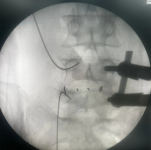

3.微创PKP技术:老年压缩性骨折球囊扩张椎体成形术

经皮球囊扩张椎体后凸成形术是我院很早就开展的一项微创技术,已经有20多年,每年手术约200例,尤其适用于老年骨质疏松引起的胸腰椎骨折;椎体转移性肿瘤(溶骨性破坏);引起疼痛症状的椎体血管瘤、多发性骨髓瘤、Kummell 症。局部麻醉,创伤小恢复快,第二天可以下床活动,迄今为止最高手术患者92岁高龄。